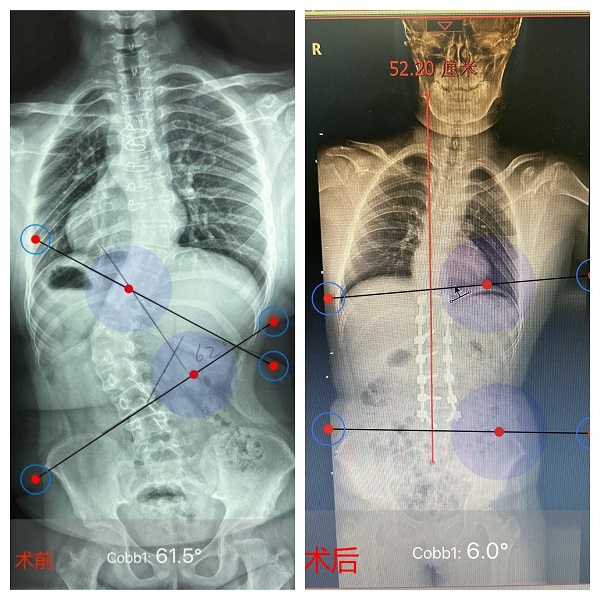

图说:仁济医院专家为脊柱侧弯患者实施矫形手术 采访对象提供(下同)

图说:患者术前62°的脊柱侧弯,术后仅为6°

术前62°的脊柱侧弯,术后仅为6°,三维透视显示丹丹的矫正效果良好。丹丹手术前身高150cm,手术后身高达到了152cm。